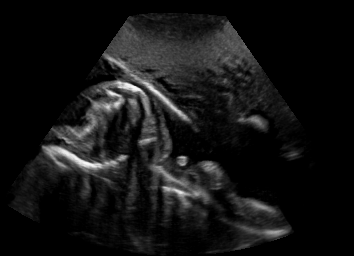

Real in-vivo images. 22 ultrasound sequences were collected using a GE Voluson E8 machine during standard fetal screening exams of 8 patients. Each sequence is several seconds long. We extracted all 4427 frames and resize them to , see Fig. 2 for some examples. The resulting image set was randomly split into training-validation-test sets by a 80-10-10% ratio.

Comparison to state-of-the-art. As seen qualitatively from the examples in Fig. 3, our method substantially outperforms the alternatives in terms of content preservation, while translating realistic US appearance. CycleGAN, SASAN, and CUT hallucinate inexistent tissue regions fail to generate fine anatomical structures, e.g. the ribs. StarGAN fails to generate faithful ultrasound speckle appearance, which leads to highly unrealistic images. Our method ConPres preserves anatomical structures, while enhancing the images with a realistic appearance. It further faithfully preserves acoustic shadows, even without explicit enforcement. However, as seen from the last column, the refraction artefact appears artificial in the images translated by all the methods. Note that although the imaging field-of-view (FoV) and probe opening in the simulation is significantly different from the real in-vivo images (Fig. 2) used for training, our ConPres maintains the input FoV closely compared to previous state-of-the-art. The results in Tab 2 quantitatively confirm the superiority of our method. Note that SSIM and FID/KID are used to measure translation performance from two different and sometimes competing aspects, with the former metric for quantifying structure preservation and the latter metrics for image realism.

Discussion. Note that, despite both being fetal images, the simulated and the real images have substantially different anatomical contents, which makes the translation task extremely challenging. Nevertheless, our proposed framework is able to generate images with appearance strikingly close to real images, with far superior realism than its competitors. Besides sim-to-real translation, given its multi-domain conditional nature, our proposed framework without any further training can also translate images between the other domains, e.g. seg-to-real or seg-to-sim, with examples presented in Fig. 5.